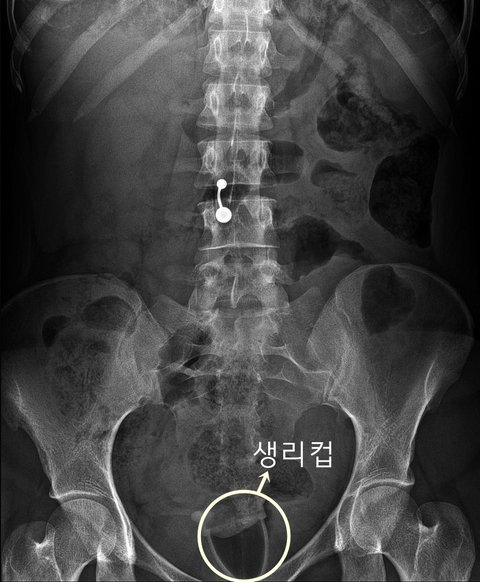

생리컵 X레이 사진

생리컵 보여서 방사선과쪽 누군가 올린듯. 또1라이네

배꼽 피어싱이 더 신기한데 .....저게 뭘까 한참 생각함